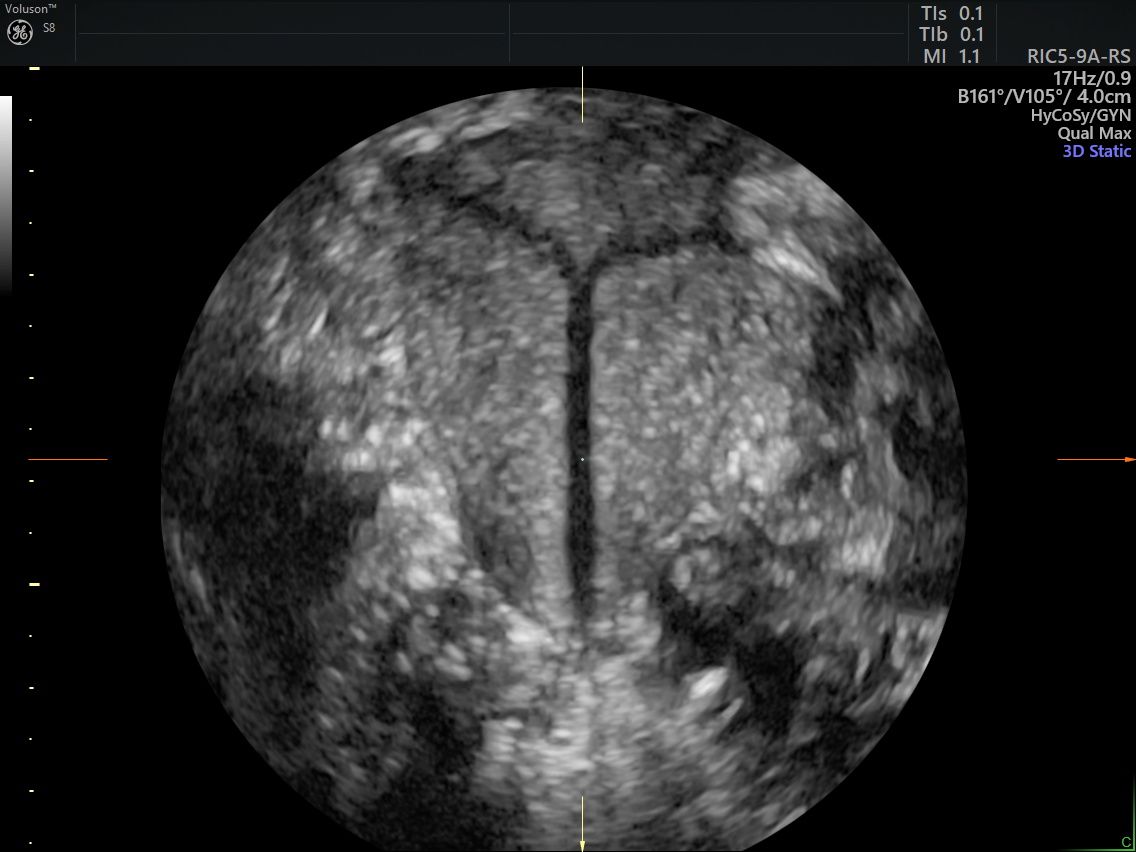

Eseguo in particolare ecografie ostetriche e ginecologiche anche in 3D e 4D per meglio identificare la problematica, offrire diagnosi precise ed un trattamento mirato e personalizzato.

• Isterosonografia

140 €